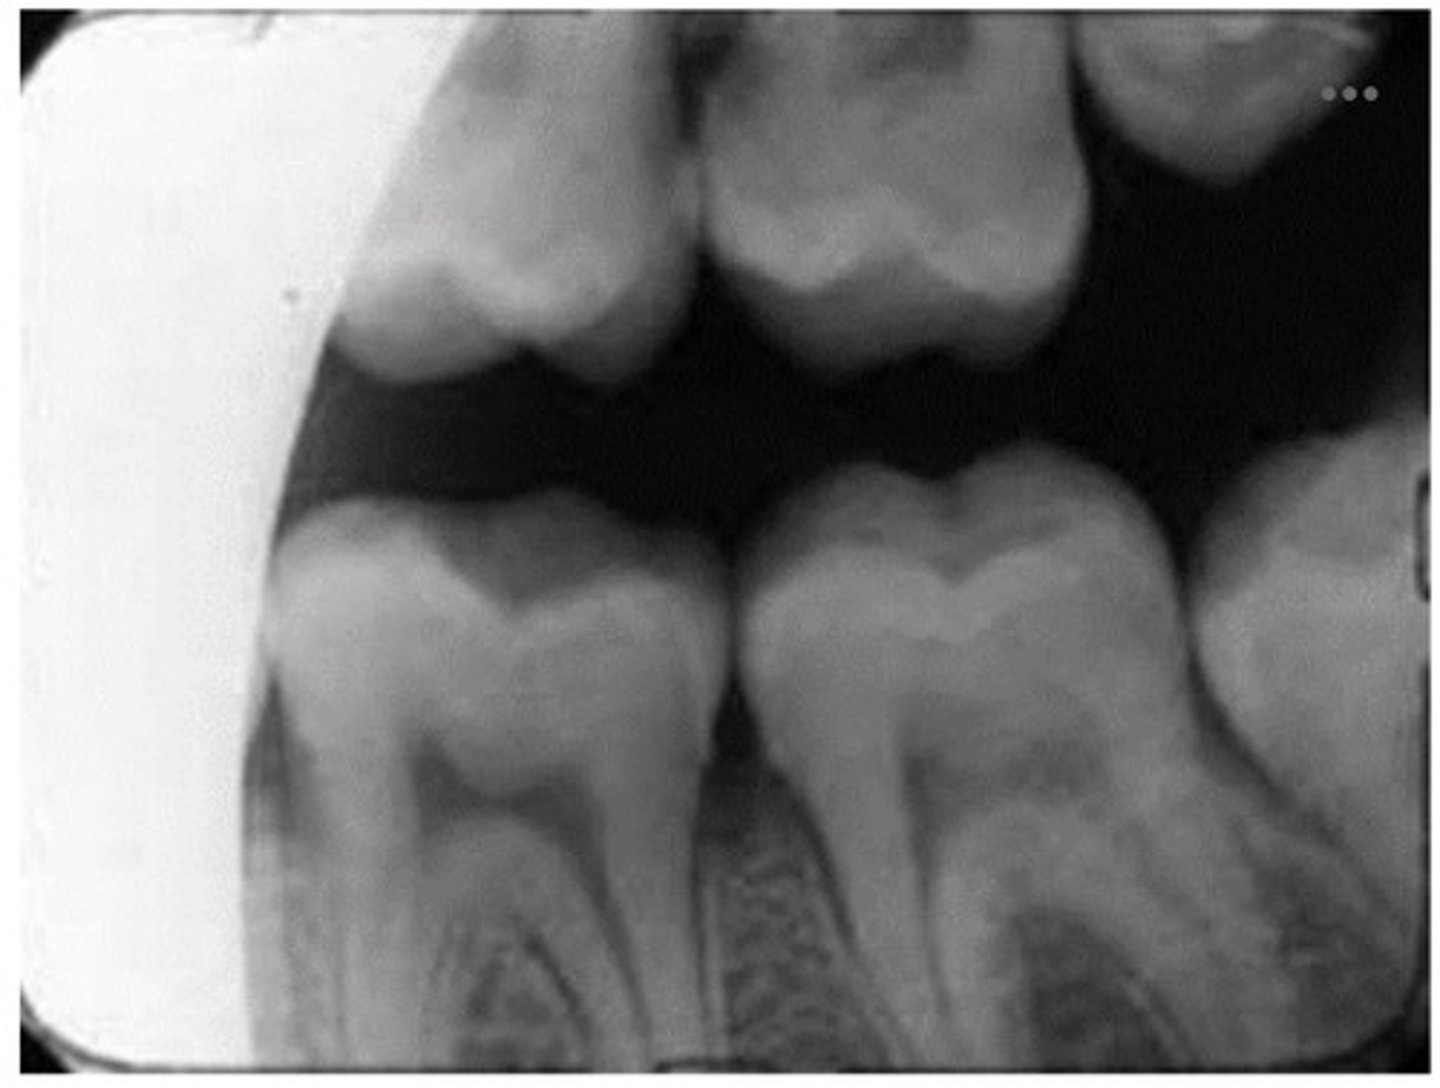

1. Identify the error seen on the dental radiograph above

2. why did this error occur?

1. cone cut

2. misalignment of the receptor with the PID